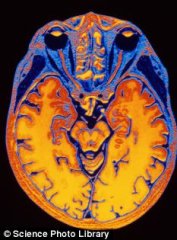

大脑大小同智力存在着无可争辩的联系——— 据《智力》杂志报道,半个多世纪以来,科学界人士一直争论着这样一个话题,即大脑的大小是否与智力有关。近日,美国科学家的一项研究证明了两者之间的关系。美国弗吉尼亚联邦大学心理学家迈克尔·麦克丹尼尔表示,...